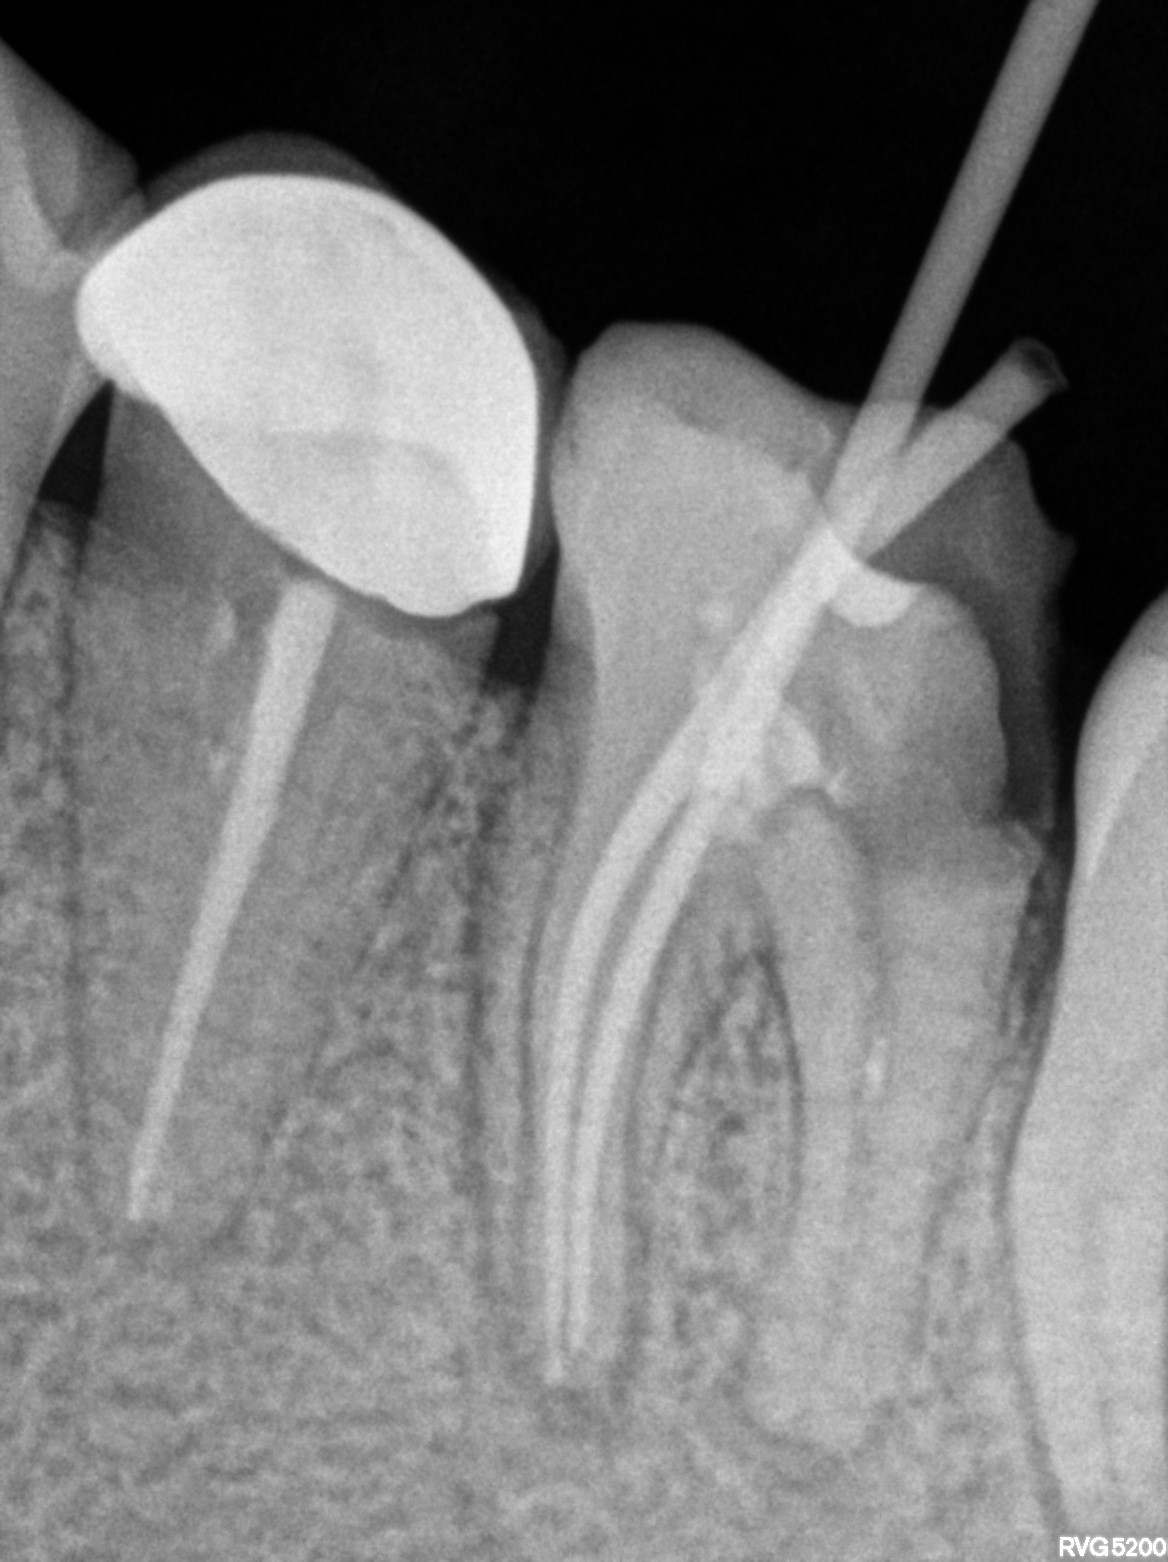

Dental Radiographs FHIR: DocumentReference · LOINC 24641-7

xray_1772203508_0.jpg

24641-7

| Root canal treatment | 234780006 | D3330 Endodontic therapy, molar tooth | ##36 | 2026-02-23 | completed | A/o 36, BMP Mesial 25.04 two canals and distal 25.06 one canal///working length mesial short file 2.5 stopper and distal short file 2.5 stopper | |

| 2026-02-23 21:31 | fulfilled | A/o 36, BMP Mesial 25.04 two canals and distal 25.06 one canal///working length mesial short file 2. — Dr Riyaz | |